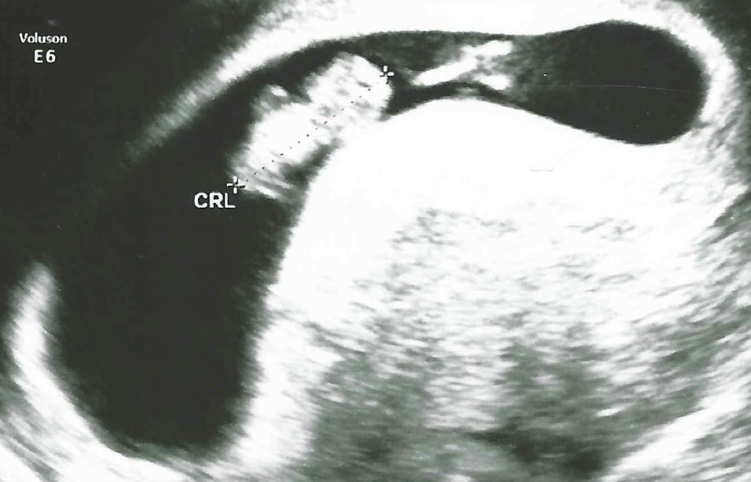

8 weken